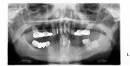

Мне 47 лет. Имею глубокий дистальный прикус (скорее всего приобретенный вследствие ранней потери корневых зубов и отсутствия своевременного протезирования) и сильную дистрофию десен нижней челюсти в зоне корневых зубов.

Сейчас повторно протезирую зубы. Все старые коронки сняты. На нижнюю челюсть будет установлен бюгельный протез. В планах поднять высоту корневых зубов. Проблем с ВНЧС нет.